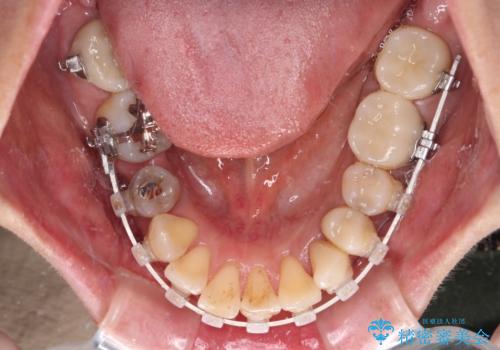

矯正治療によって前歯にスペースを作り、左右対称となるようにオールセラミッククラウンにて補綴治療を行うとしました。

他にも奥歯の咬み合わせに問題があったので、全顎的な矯正治療を行い、前歯以外にも口を開けたときに目立つ奥の銀歯をセラミッククラウンにて補綴治療を行うこととしました。

前歯の横幅が大きいことも気になっていたので、矯正治療で前歯5本の幅をコントロールしながら移動させ、治療開始前より一回りサイズの小さいセラミッククラウンを装着することができました。